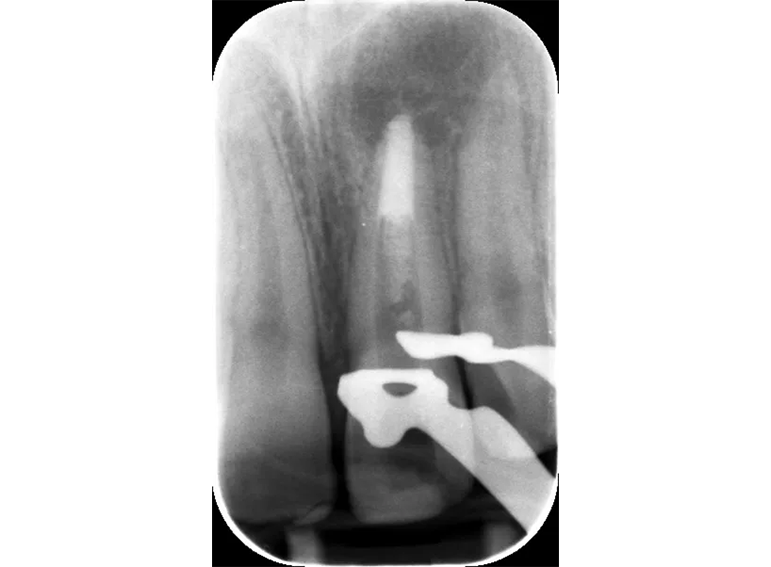

Root canal treatment including apexification of an immature incisor following dental trauma.